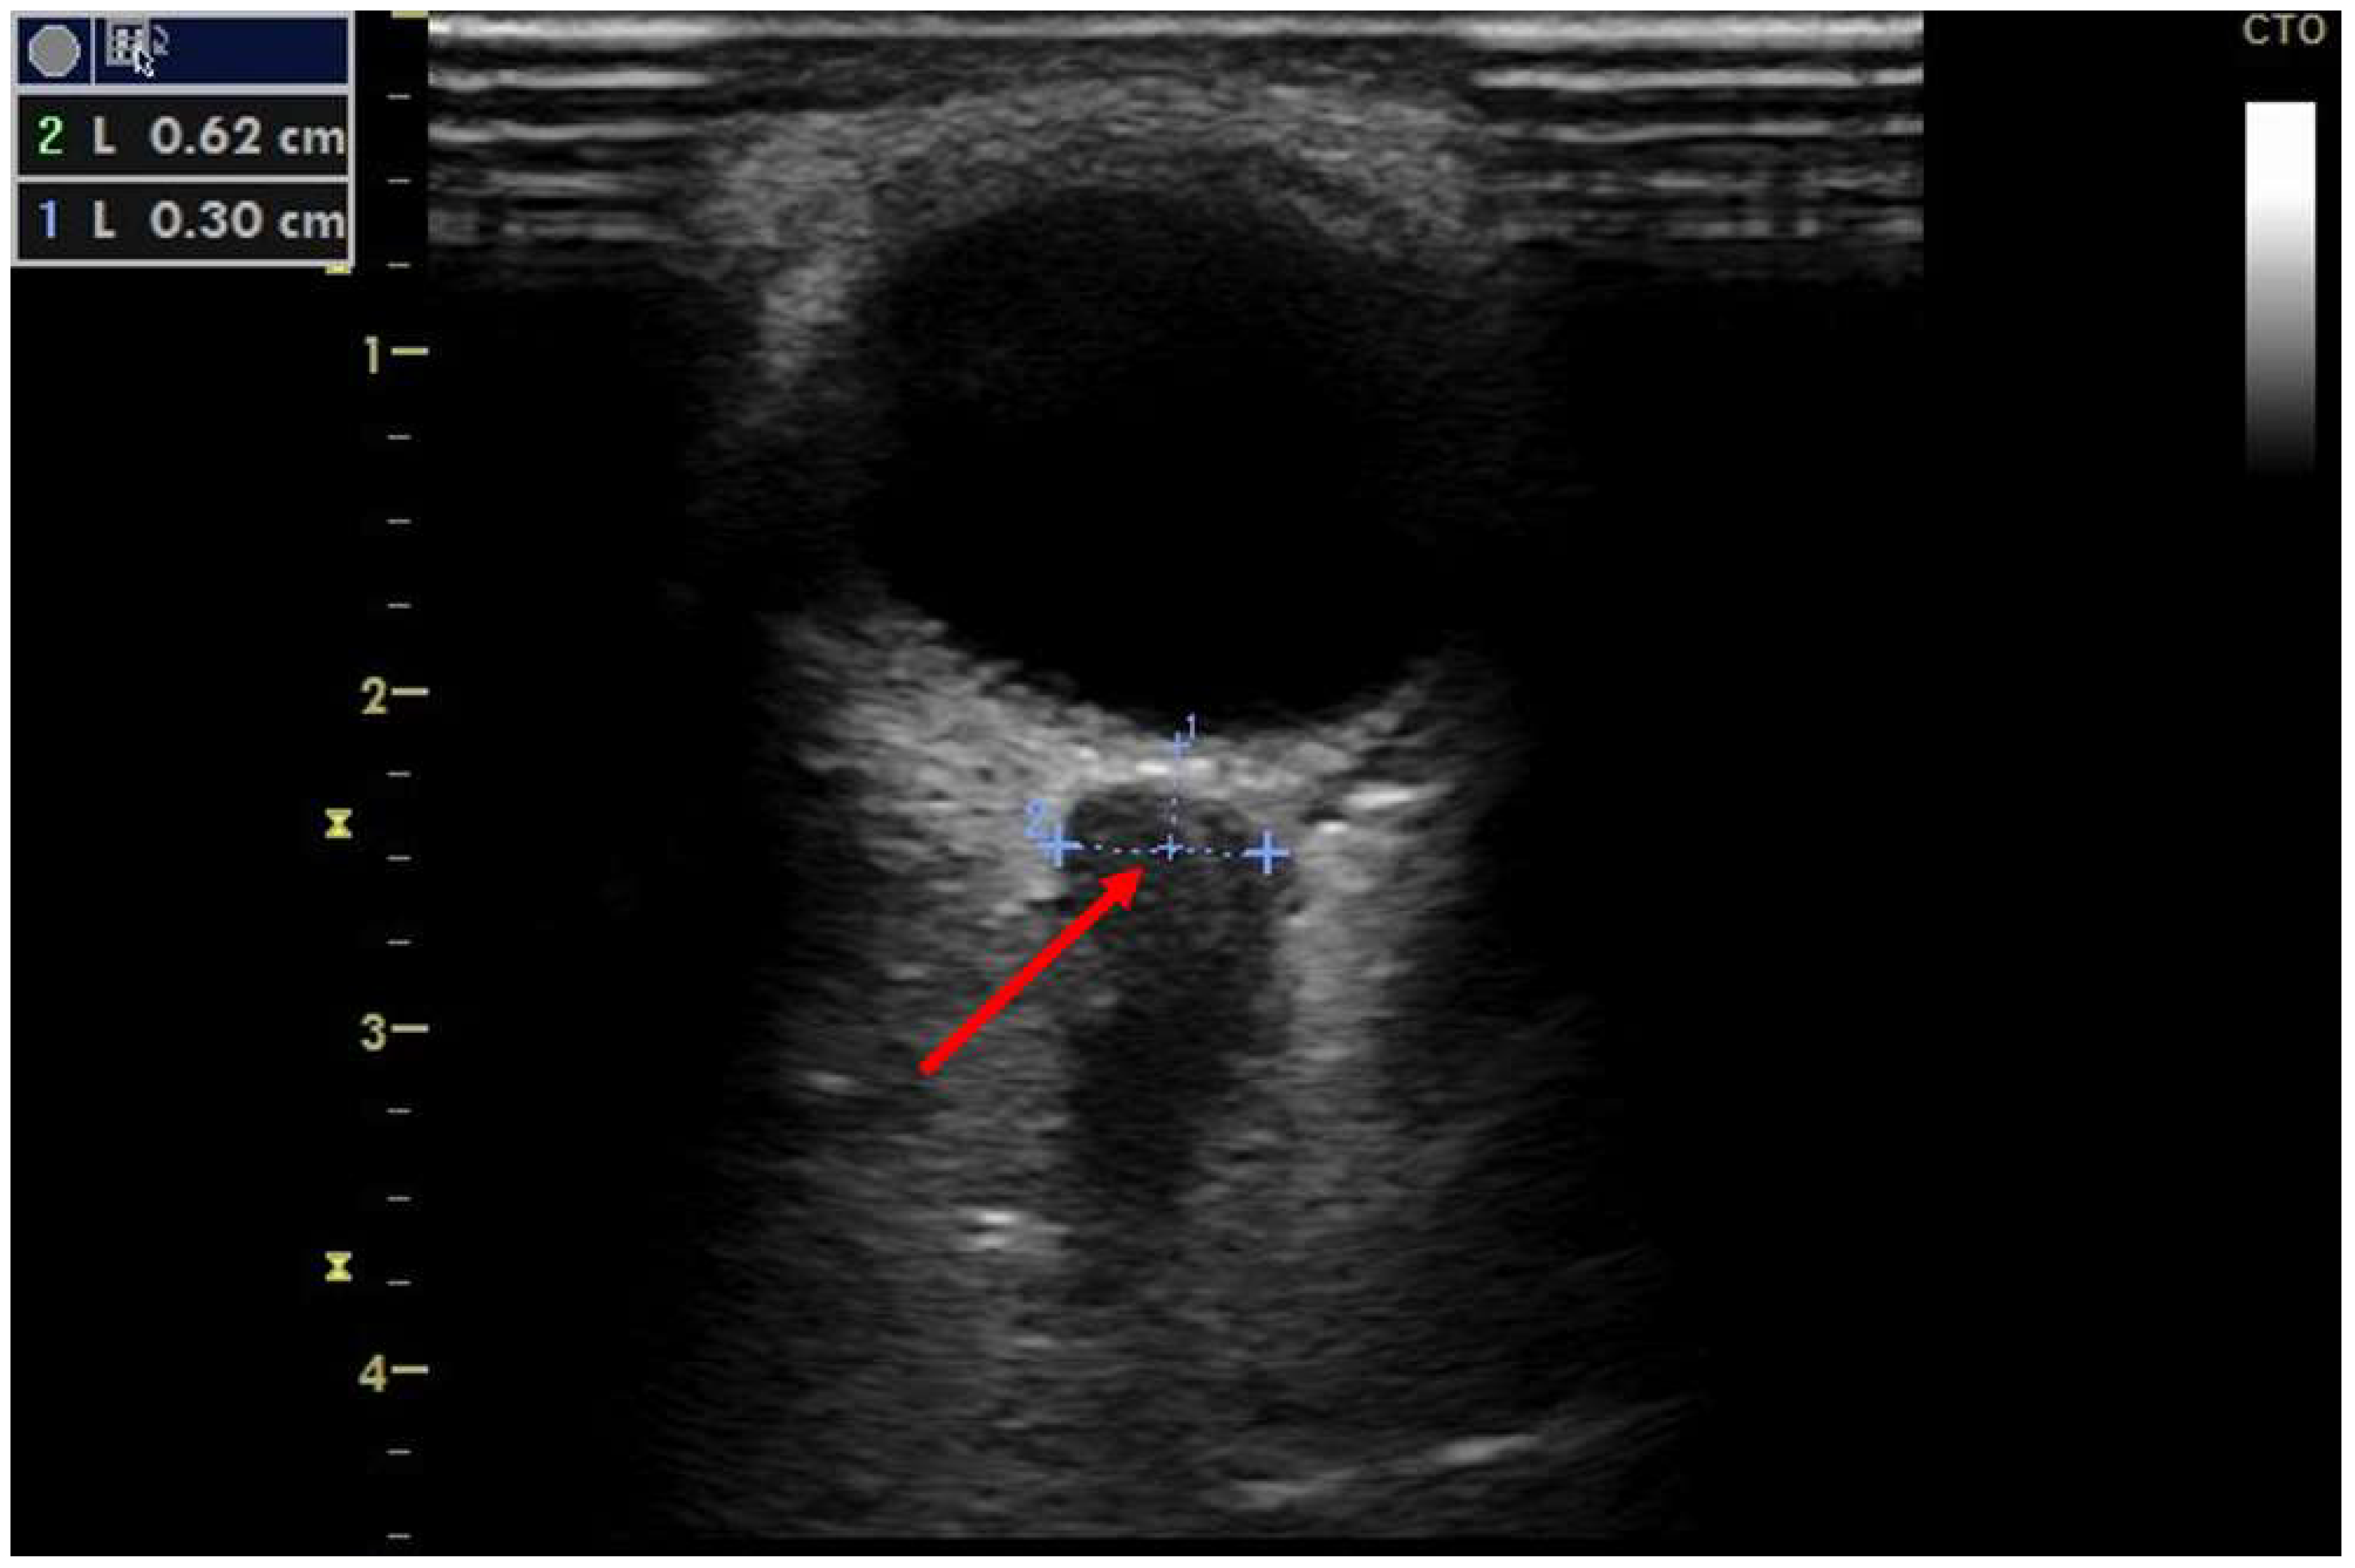

3. Results

Figure 1. Ocular ultrasound in patient #1. Ocular ultrasound image. Optic nerve sheath diameter is measured 3 mm behind the globe at 6.2 mm (red arrow), indicating intracranial pressure above 20 mmHg.